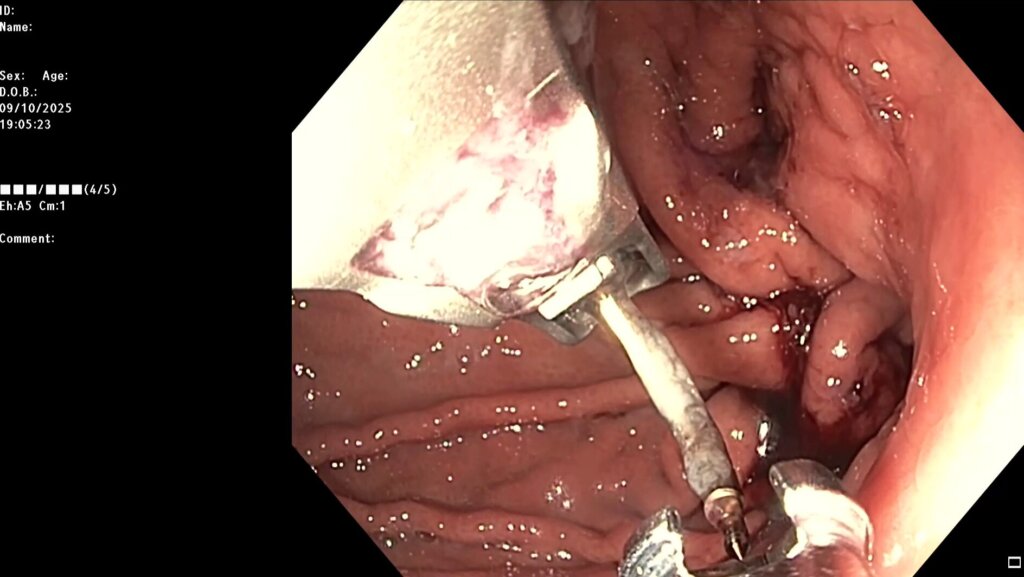

После предварительного обследования произведена операция: ESG + АПК (APC) свода; всего использовано 6 швов, время процедуры ≈ 120 минут.

Комбинированный метод представляет собой эндолюминальное ушивание желудка (формирование «рукава») с добавлением локальной аргоноплазменной коагуляции (АПК, APC — поверхностная неконтактная термальная абляция слизистой) в зоне свода желудка с целью индуцирования контролируемого фиброза и снижения секреции грелина. ESG выполняется перорально под визуальным контролем с использованием системы Overstitch;

Под видеоконтролем выполнена эндоскопическая рукавная гастропластика: сшивание стенок желудка при помощи аппарата Overstitch Boston Scientific по длине тела с целью уменьшения объёмов съедаемой пищи.